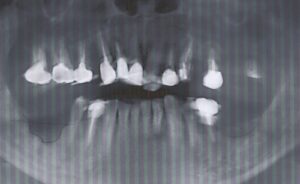

62歳男性

Underbite, crumbling teeth, orthodontics

咬合高径をあげれば受け口が改善される

ただし、奥歯には補綴が必要になる